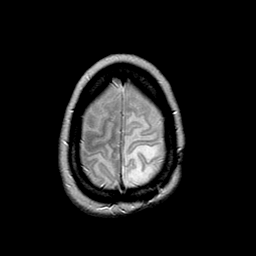

MR Study #2 -- Slice #45